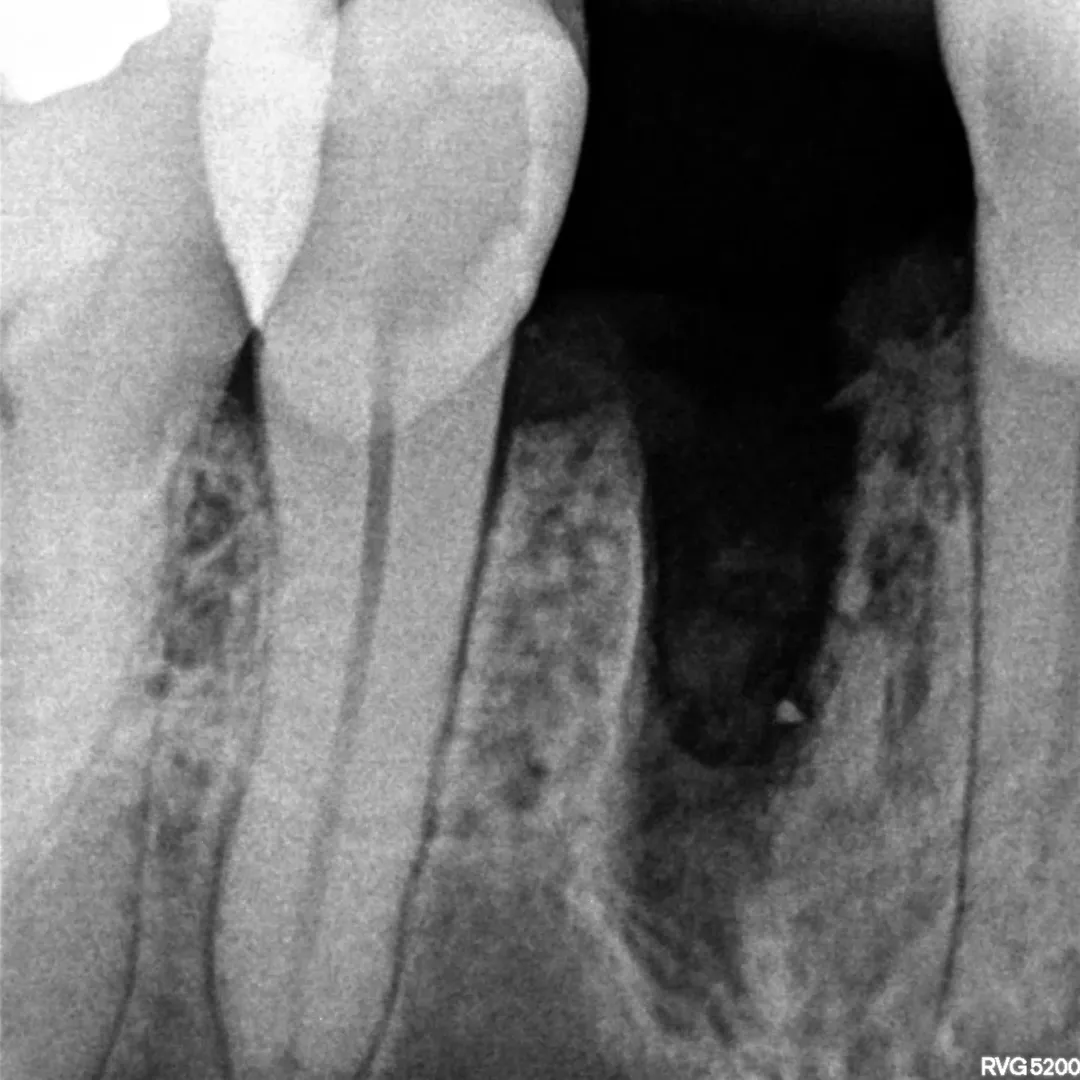

O paciente apresentava um dente comprometido que necessitava de extração. Nas radiografias periapicais, era visível o comprometimento da estrutura dentária, mas as tábuas ósseas circundantes encontravam-se preservadas, o que abria a porta para uma abordagem imediata.

Nas imagens, é possível acompanhar a sequência completa: desde as radiografias iniciais com o dente comprometido, passando pela fase cirúrgica com a extração e colocação do implante, até ao provisório aparafusado em posição. A radiografia final confirma o bom posicionamento do implante e o preenchimento adequado do gap vestibular.